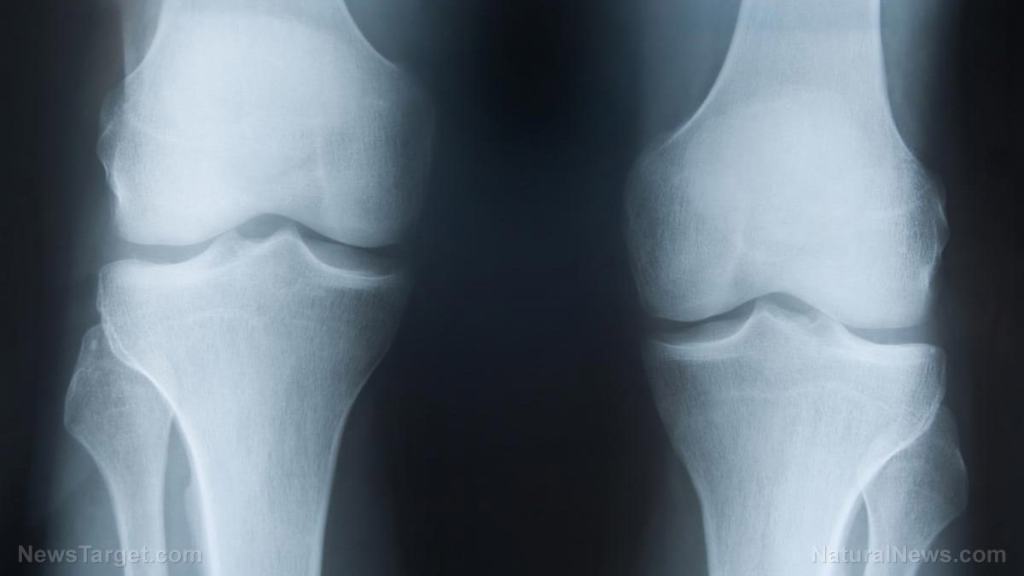

The woman told them that she had developed serious inflammatory symptoms such as redness, warmth, swelling, pain, and loss of function in her right knee joint, which proceeded to migrate to her left wrist, then to her right wrist, and eventually to her right Achilles tendon. This traveling disease, if you will, is described as migratory polyarthralgia.